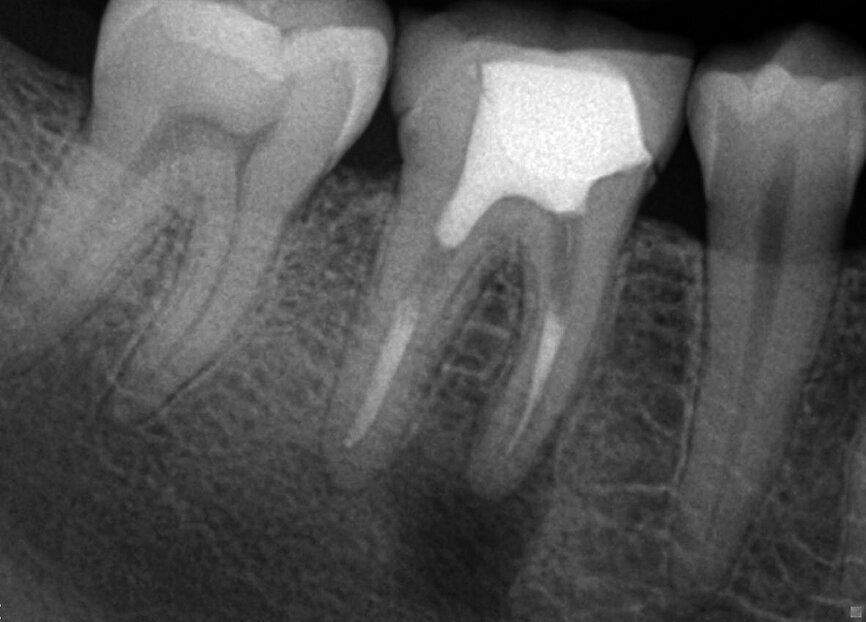

Fig. 4: Complexity of the apical area manifests itself after it was treated chemically, dried, and sealed by way of the warm vertical technique.